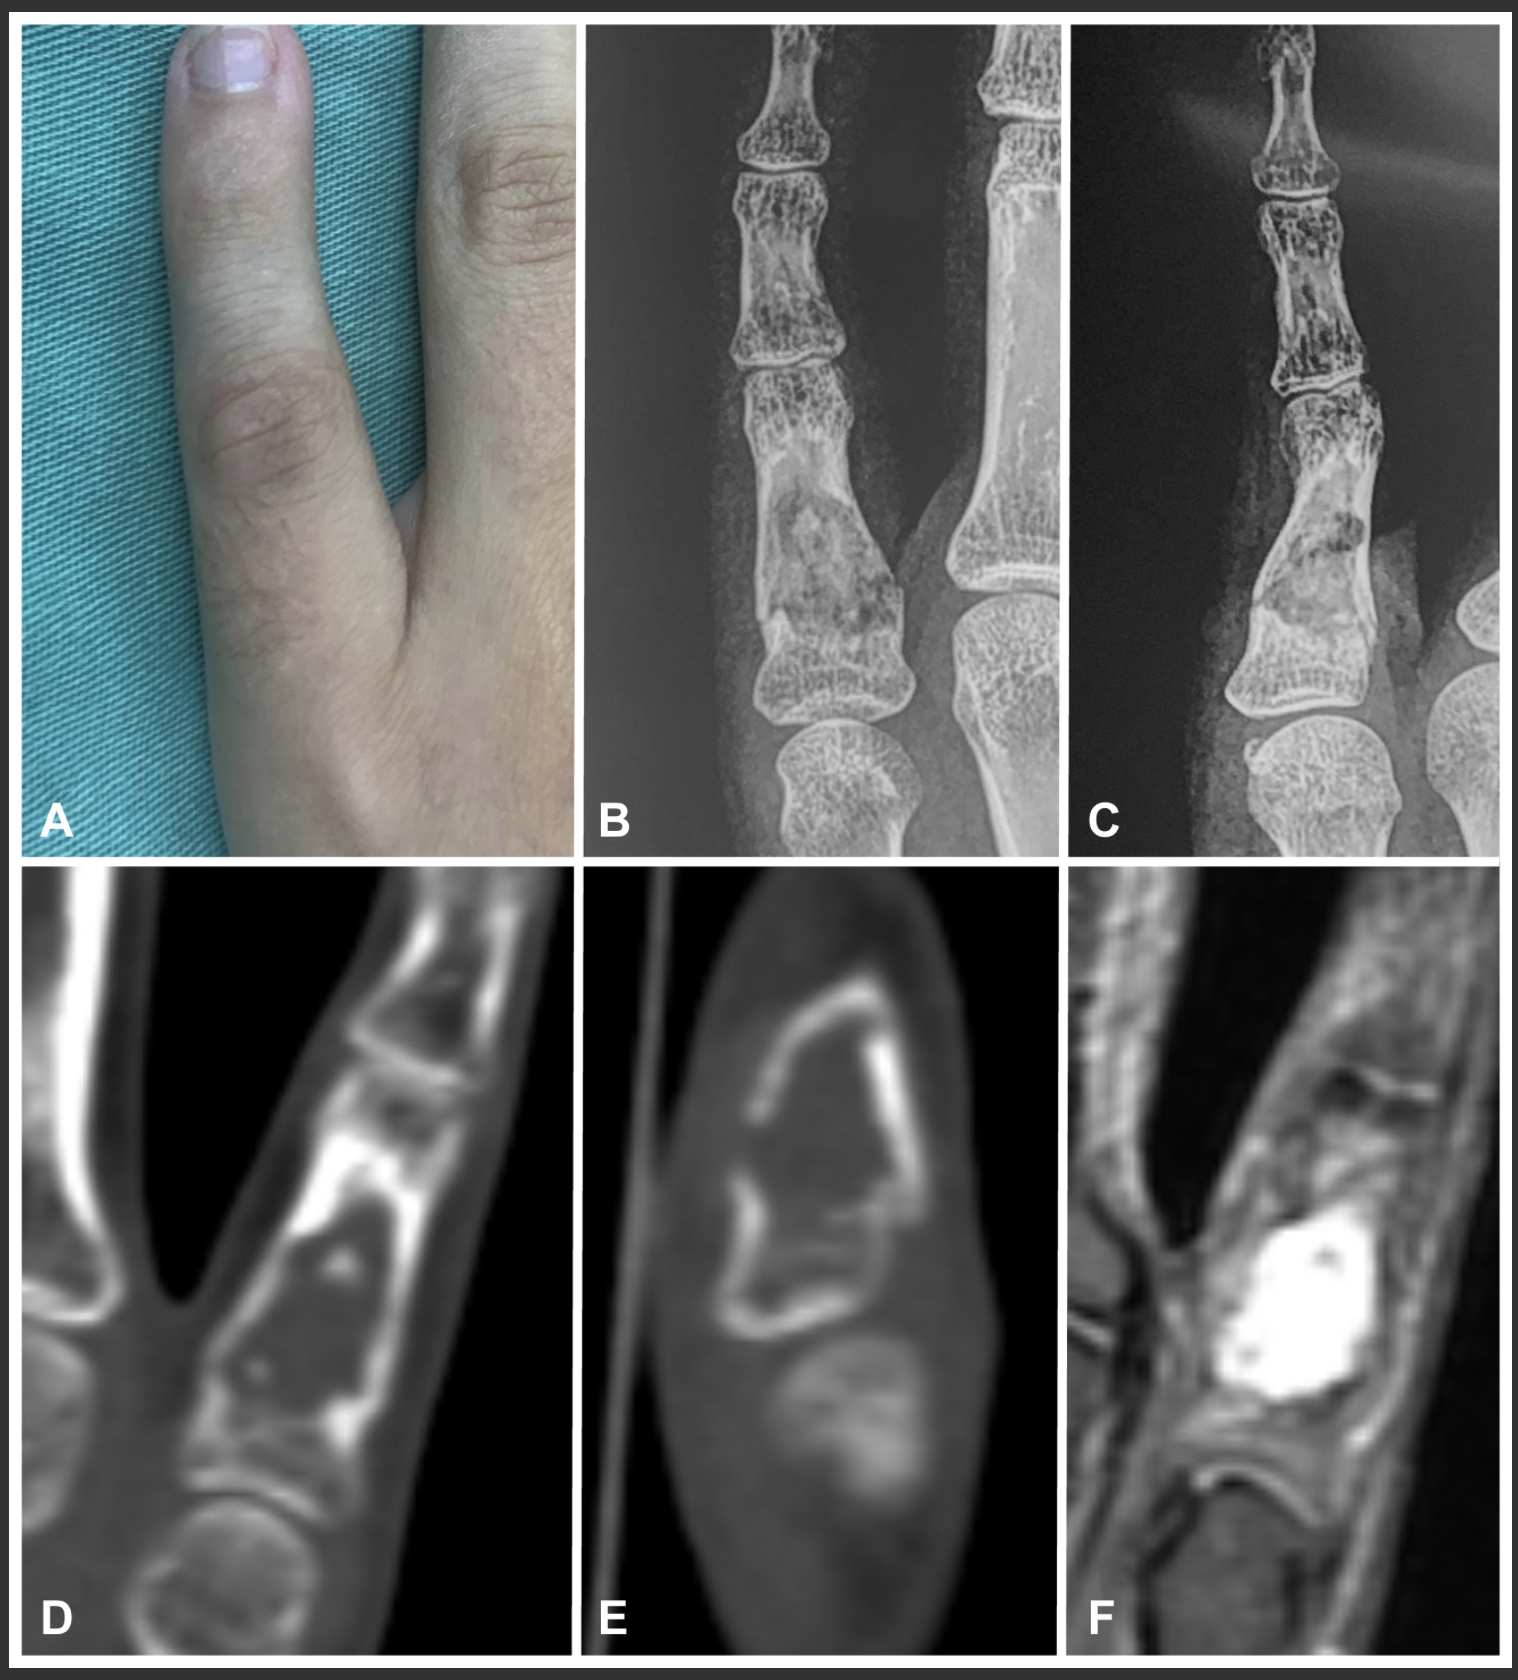

上腕骨からキノコ状に隆起しているのが腫瘍です.

遺伝性多発性外骨腫の上腕骨腫瘍の切除術でした.